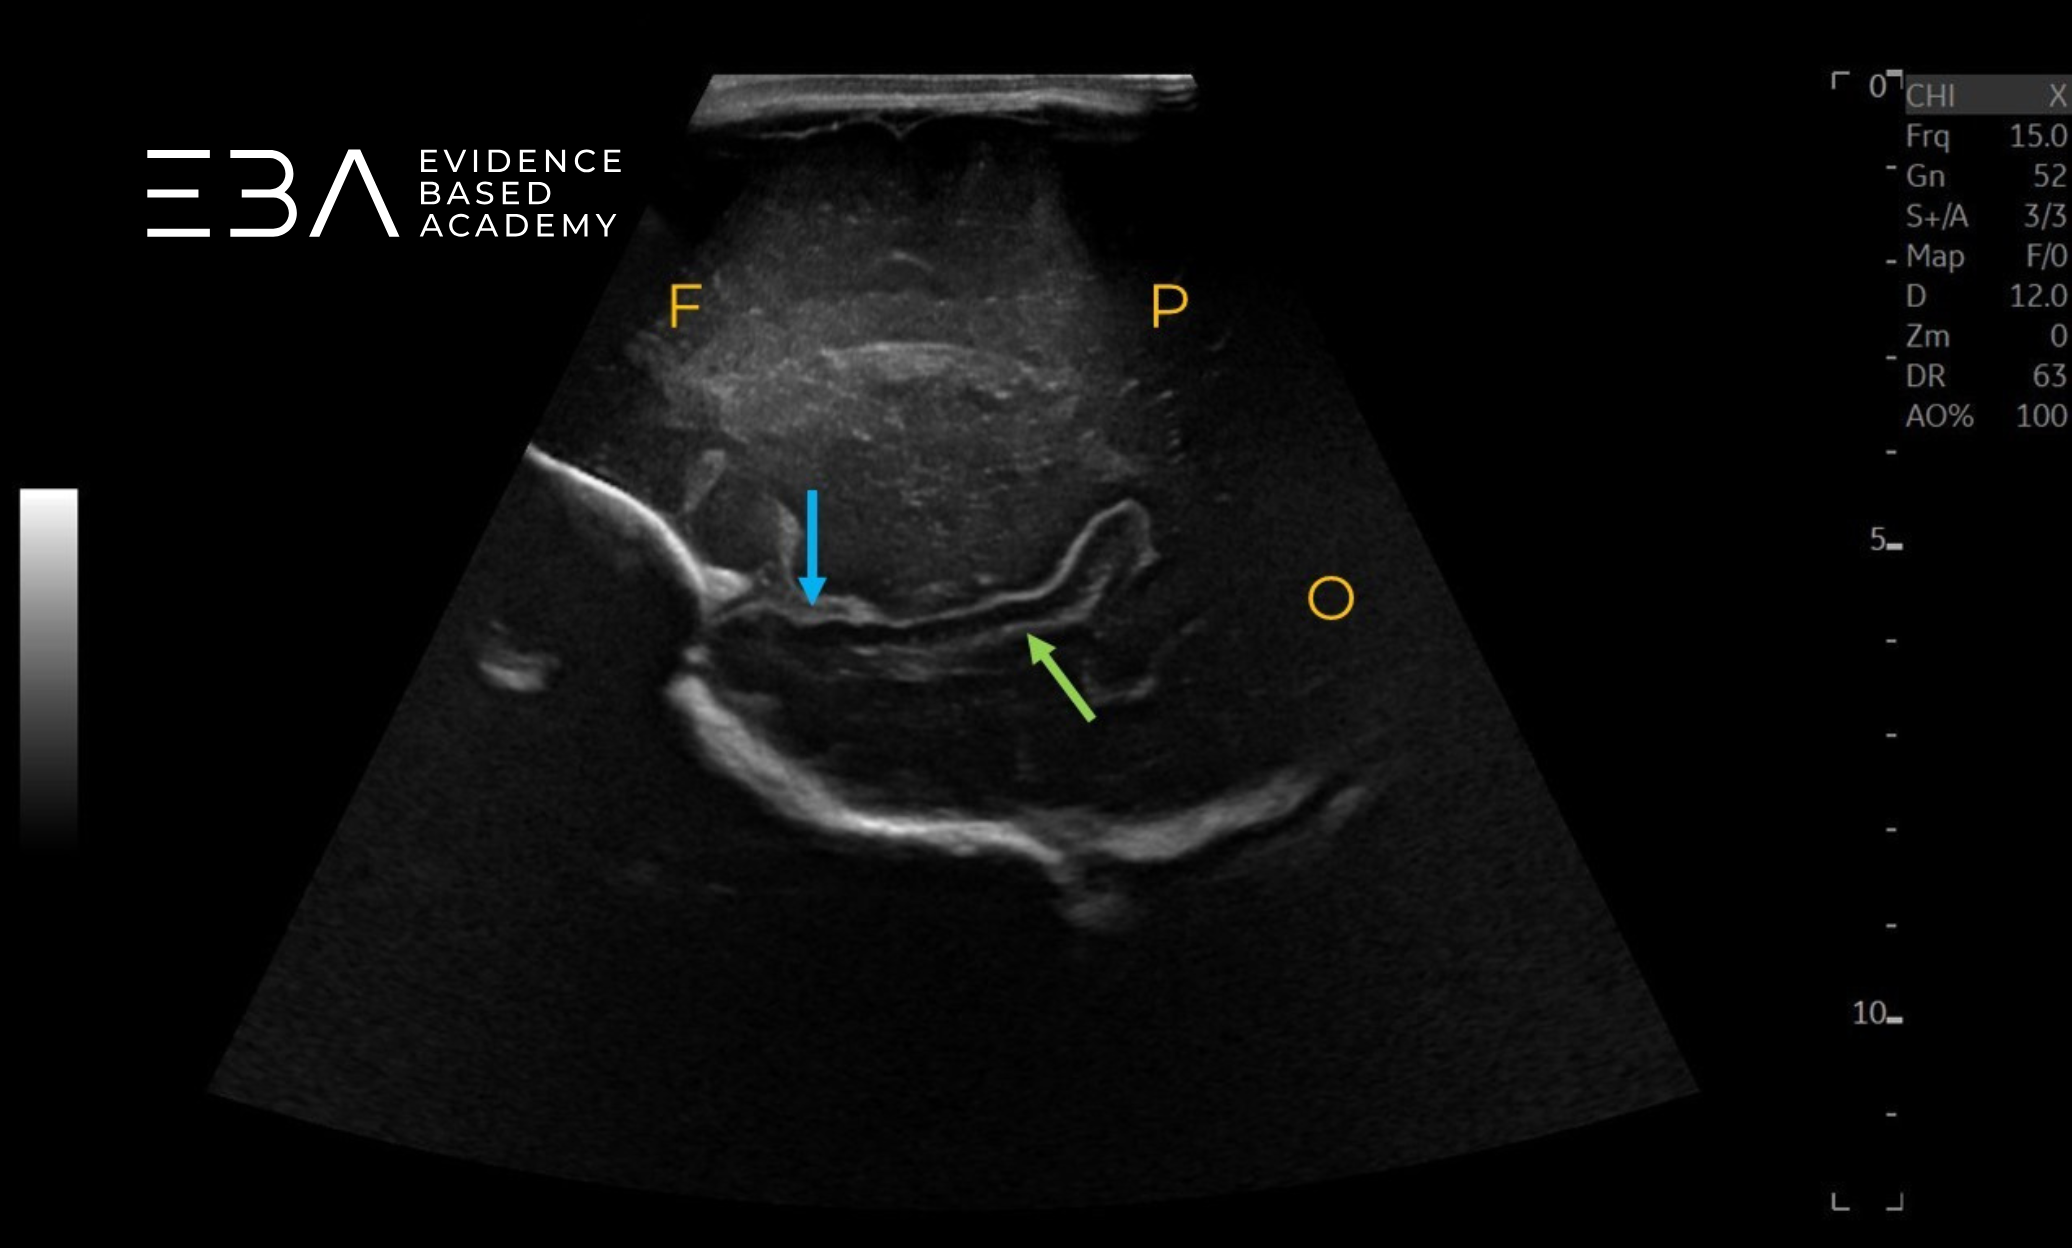

Projekcje przystrzałkowe – wykonujemy po 2–3 obrazy po każdej stronie, stopniowo oddalając się od linii pośrodkowej, od bruzdy wzgórzowo-ogoniastej do szczeliny Sylwiusza (6). Uwidaczniamy komorę boczną, splot naczyniówkowy, a na obrazach bardziej bocznych – rogi potyliczne i skroniowe komór bocznych oraz płaty czołowy, skroniowy, ciemieniowy i potyliczny (3, 6).

zdj. 17

Głowica liniowa – projekcja przystrzałkowa. F – płat czołowy, P – płat ciemieniowy, O – płat potyliczny. Strzałką zaznaczono zakręt obręczy.

zdj. 18

Głowica liniowa – projekcja przystrzałkowa. Zakręt czołowy górny (niebieska strzałka), płacik okołośrodkowy (żółta strzałka), zakręt obręczy (zielona strzałka) przedklinek (czerwona strzałka), zakręt językowaty (fioletowa strzałka).

zdj. 19

Głowica liniowa. Niebieską strzałką zaznaczono róg czołowy komory bocznej, żółtą strzałką zaznaczono płat skroniowy, zieloną strzałką zaznaczono wzgórze.

zdj. 20

Głowica liniowa – projekcja przystrzałkowa. Zieloną strzałką zaznaczono oczodół, żółtą strzałką zaznaczono wzgórze.

zdj. 21

Głowica liniowa – projekcja przystrzałkowa. F – płat czołowy, P – płat ciemieniowy, O – płat potyliczny. Bruzda boczne (niebieska strzałka), płat skroniowy (zielona strzałka).